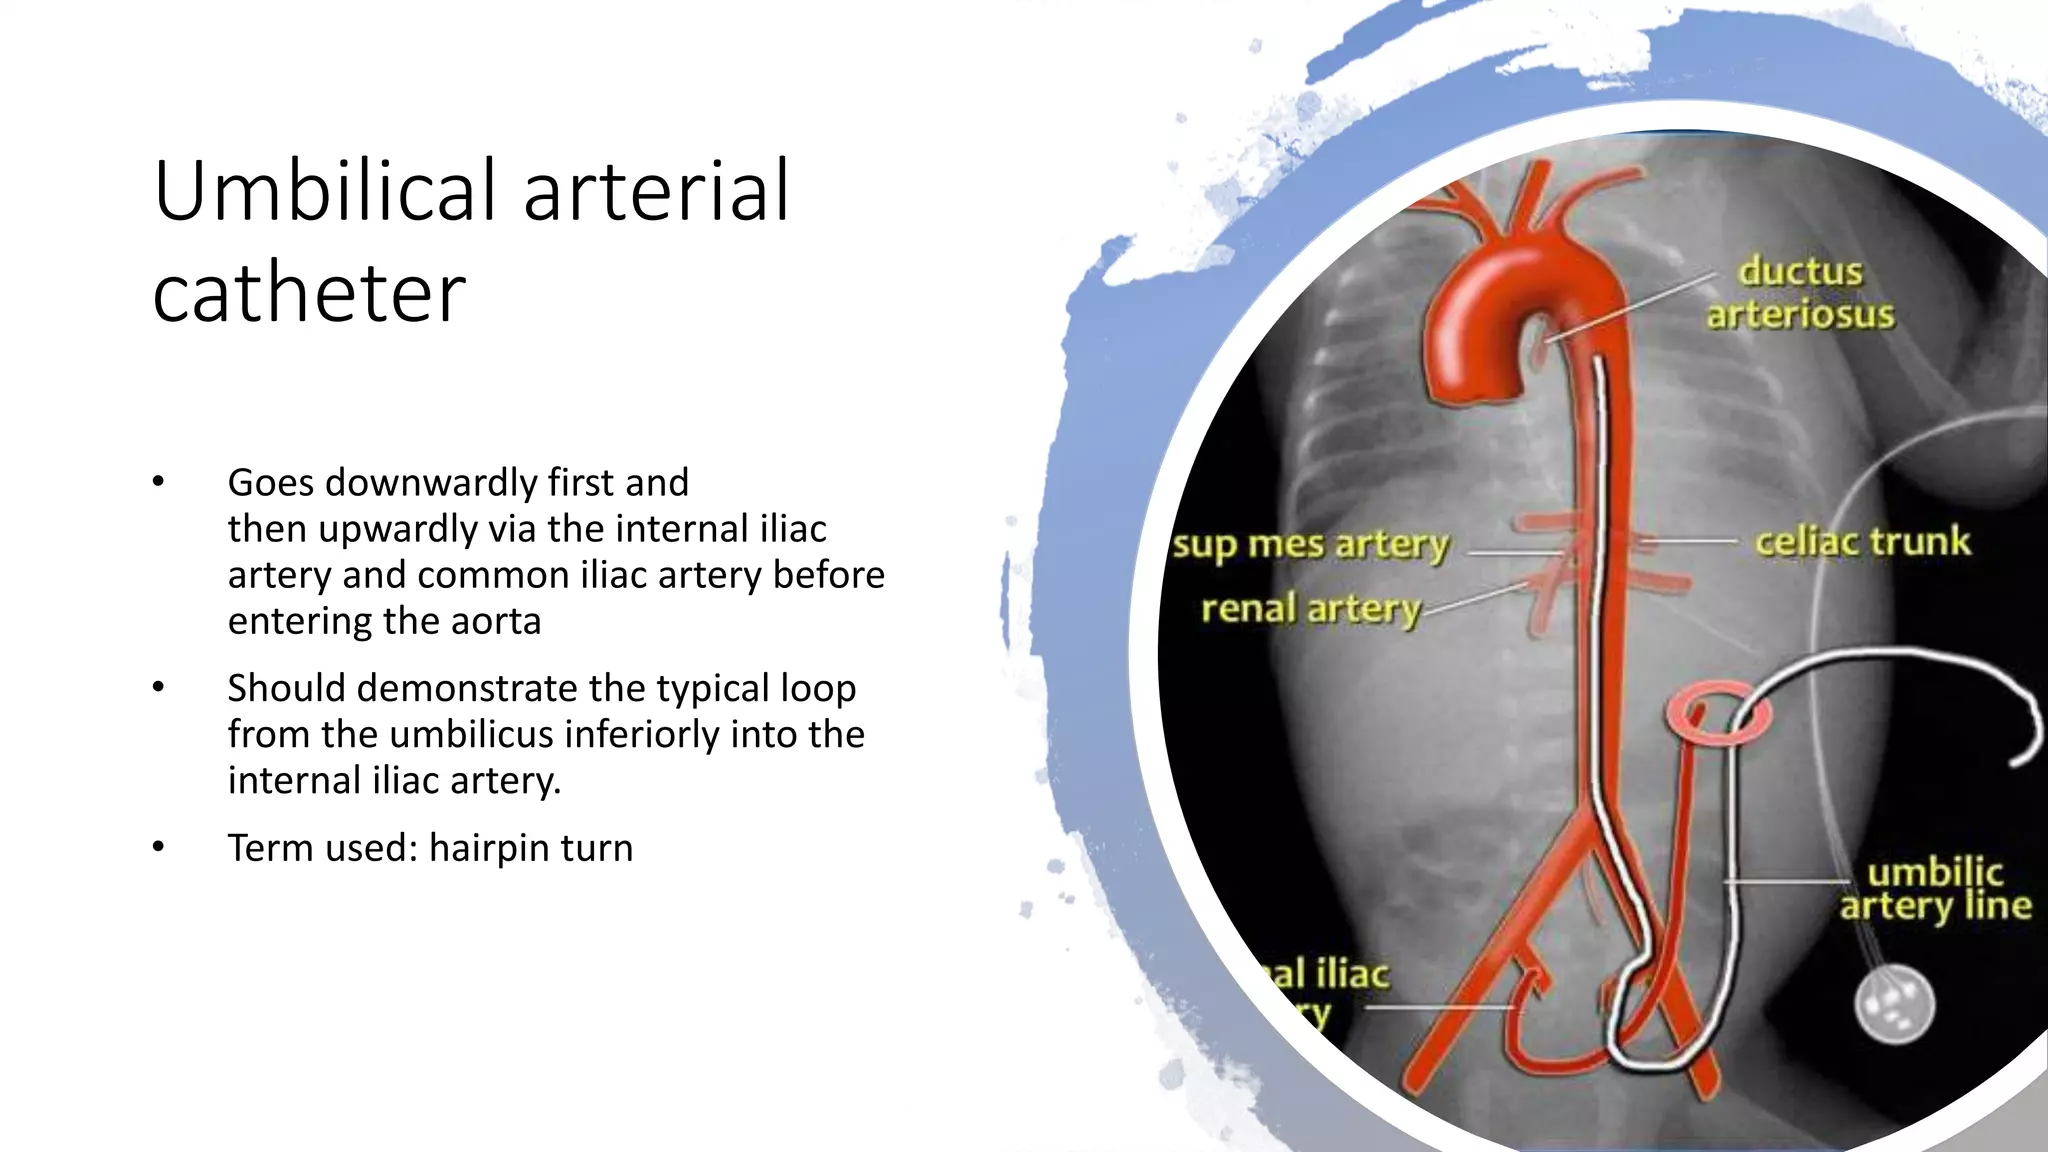

This document provides an overview of neonatal chest x-rays, including when they should and should not be performed, what a normal x-ray looks like, common positions of tubes and catheters, and common causes of respiratory distress in neonates. It discusses the appearance of a normal chest x-ray as well as conditions like respiratory distress syndrome, transient tachypnea of the newborn, meconium aspiration syndrome, and pneumonia. Surgical conditions like diaphragmatic hernia and esophageal atresia are also reviewed.